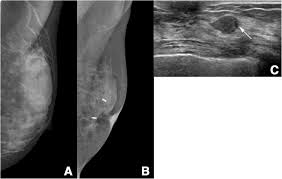

Screening with 3d mammography seemed to find breast cancers at an earlier, more treatable stage in these younger women. After a mammogram that didn't show anything, and a sonogram that found the lump, i was diagnosed with stage 2 breast cancer. Overall, screening mammograms do not find about 1 in 5 breast cancers. Breast cancers found by screening are generally at an early stage. Breast cancers are sometimes detected when very small by the presence of microcalcifications in the breast. Mammography is good at finding breast cancer, especially in women ages 50 and older. The earliest a tumor may be found on a mammogram is when it is between 0.2 cm and 0.3 cm in diameter. Unlike typical breast cancer, ibc usually cannot be detected by a mammogram or ultrasound. Thus, approximately 20% to 28% of breast cancers are interval cancers. Half of women have dense breast tissue, and for those women, mammogram may not be enough. Studies indicate that combining a 3d mammogram with a standard mammogram can result in about one more breast cancer for every 1,000 women screened when compared with standard mammogram alone. Breast cancer is primarily a women's disease, but it does affect men. State that screening reduces breast cancer mortality by 20% or more, because it sounds more impressive than explaining that the absolute risk reduction is 1 in 1,000.

Mammograms May Lead To Breast Cancer Over Diagnosis Study Finds Shots Health News Npr from media.npr.org Little attention has been paid to how interval breast cancers are ultimately discovered. Percent of women aged 40 and over who had a mammogram within the past 2 years: We estimate about 15 percent of breast cancers are diagnosed during a reasonable interval after a negative mammogram. Breast cancers are sometimes detected when very small by the presence of microcalcifications in the breast. The average size of breast cancer, when found on mammograms, is 1.1 cm. Half of women have dense breast tissue, and for those women, mammogram may not be enough. It's so important to listen to the messages our bodies are telling. Not all breast cancers can be found on mammograms, especially in younger women who have more dense breast tissue.

This type of mammogram is called a diagnostic mammogram. Breast cancer is the most common cancer in the uk, accounting for 15% of all new cancer cases (2017). Improve breast cancer detection in dense breast tissue. A breast lump is probably cancer. We estimate about 15 percent of breast cancers are diagnosed during a reasonable interval after a negative mammogram. After a mammogram that didn't show anything, and a sonogram that found the lump, i was diagnosed with stage 2 breast cancer. Screening with 3d mammography seemed to find breast cancers at an earlier, more treatable stage in these younger women. Mammography women diagnosed with breast cancer after having yearly mammograms were diagnosed with cancers that were smaller and less advanced than women who had mammograms every 2 years, according to results from a small study. The current evidence suggests that breast screening reduces the number of deaths from breast cancer by about 1,300 a year in the uk. Luminal a tumors are associated with the most favorable prognosis Little attention has been paid to how interval breast cancers are ultimately discovered. It said 1 million women. The earliest a tumor may be found on a mammogram is when it is between 0.2 cm and 0.3 cm in diameter.

Mammography is good at finding breast cancer, especially in women ages 50 and older. It's rare for women to get cancer within a year of mammography, but it does. A breast lump is probably cancer. Percent of women aged 40 and over who had a mammogram within the past 2 years: For women age 40 to 49: Mammography women diagnosed with breast cancer after having yearly mammograms were diagnosed with cancers that were smaller and less advanced than women who had mammograms every 2 years, according to results from a small study. This type of mammogram is called a diagnostic mammogram. Thus, approximately 20% to 28% of breast cancers are interval cancers. The woman who has inflammatory breast cancer has breast cancer that's red and inflamed, with an angry look to the breast cancer, he says. Unlike typical breast cancer, ibc usually cannot be detected by a mammogram or ultrasound. It said 1 million women. Mammograms miss about 15 percent of. Breast cancer is primarily a women's disease, but it does affect men.